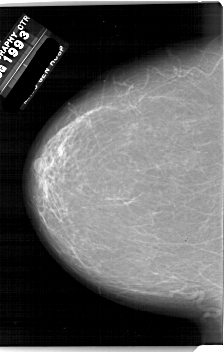

A_1857_1.RIGHT_MLO

RIGHT_MLO LINES 6871 PIXELS_PER_LINE 4981 BITS_PER_PIXEL 12 RESOLUTION 43.5 OVERLAY

FILE: A_1857_1.RIGHT_CC.OVERLAY

TOTAL_ABNORMALITIES 1

ABNORMALITY 1

LESION_TYPE MASS SHAPE IRREGULAR MARGINS ILL_DEFINED

ASSESSMENT 4

SUBTLETY 3

PATHOLOGY BENIGN

TOTAL_OUTLINES 1

BOUNDARY